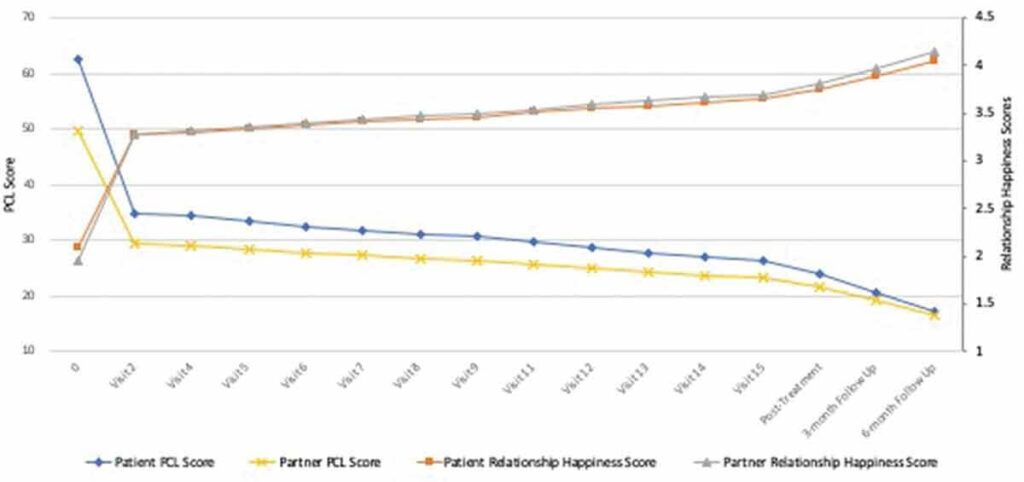

試験後の評価では、治療前の平均PTSDスコアが41.42点だったのに対し、治療後には19.37点まで低下し、6ヶ月後のフォローアップでも15.52点という低い水準を維持していました。また、効果サイズ(Cohen’s d)は1.88から2.25という非常に高い数値を示しています。

患者自身による評価ではさらに顕著な改善が見られ、治療前の62.64点から治療後には23.96点、6ヶ月後には17.20点まで低下しました。効果サイズは実に2.72から3.59に達し、これは過去のMDMA個人療法の研究(d=約1.20)や、MDMAを使用しないCBCT単独(d=1.82)と比較しても、はるかに大きな改善効果を示しています。

興味深いことに、パートナーによる評価でも同様の改善傾向が確認されたとのこと。パートナーの評価では治療前の49.58点から6ヶ月後には16.64点まで低下し、効果サイズは1.85から2.72という高い数値を記録しています。これは、患者の改善が客観的にも観察可能であることを示しています。

関係満足度の改善も印象的でした。患者の関係満足度スコアは治療前の105.37点から6ヶ月後には130.78点まで上昇し、パートナーのスコアも98.10点から130.10点へと改善しました。ベースライン時点で関係に不満を抱えていた患者2名のうち、治療後には両名とも満足な関係性を報告しています(PTSD診断が残った1名を除く)。

特筆すべきは、関係の幸福度を測る単一項目の評価において、患者では効果サイズが1.42から2.79、パートナーでは1.30から1.78という極めて高い数値を示したことです。これは、この治療法が単にPTSD症状を軽減するだけでなく、カップルの関係性の質を根本的に向上させる可能性を示唆しています。